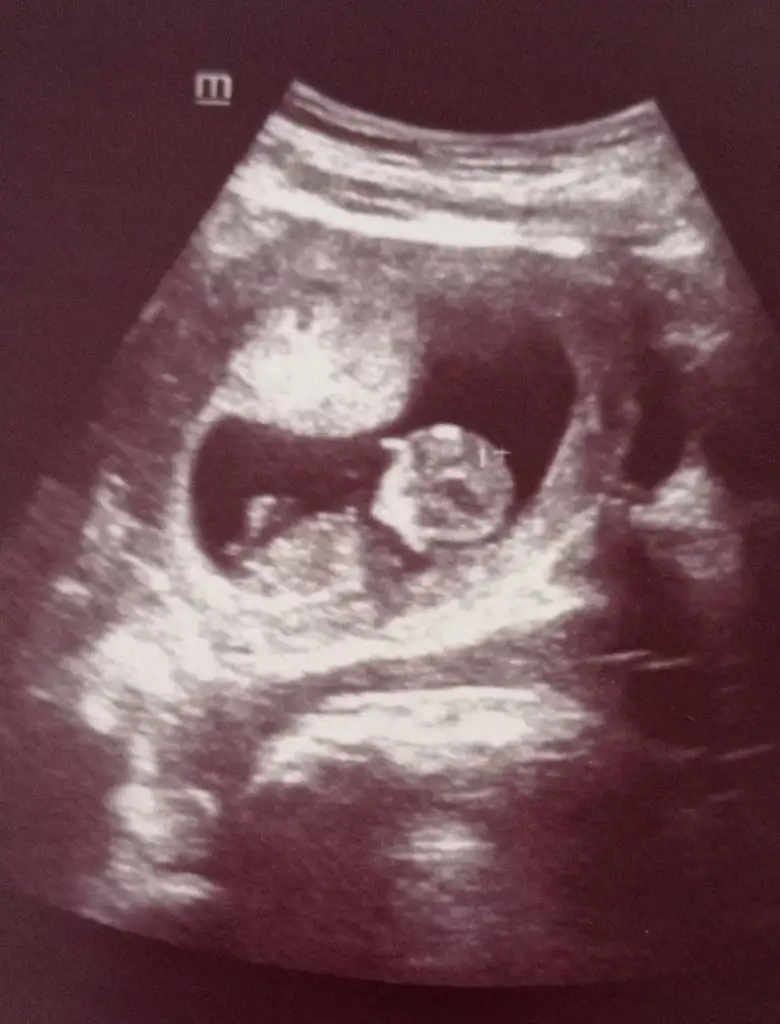

Emin olamadım kız sankiEki Görüntüle 2896743 cinsiyetini çok merak ediyorum bakabilirmisiniz

Erkek gibi sanki emin olamadım en iyi 11 12 13 haftalarEki Görüntüle 2896935 merhabalar tahmininizi alabilir miyim. SAT a göre 13+1 usg de 14 çıktı